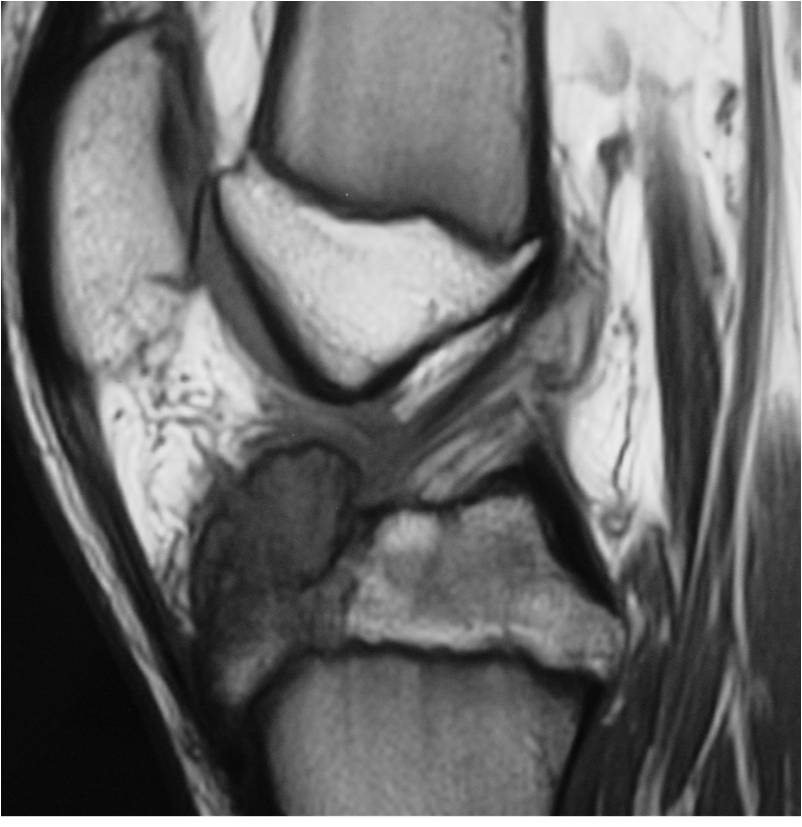

General Information Enchondroma is a benign indolent intramedullary hyaline cartilage neoplasm Accounts for 10% of all benign osseous tumors Limited growth, most lesions are less than 5 cm in maximal dimension Bones grow from a cartilaginous growth plate that...